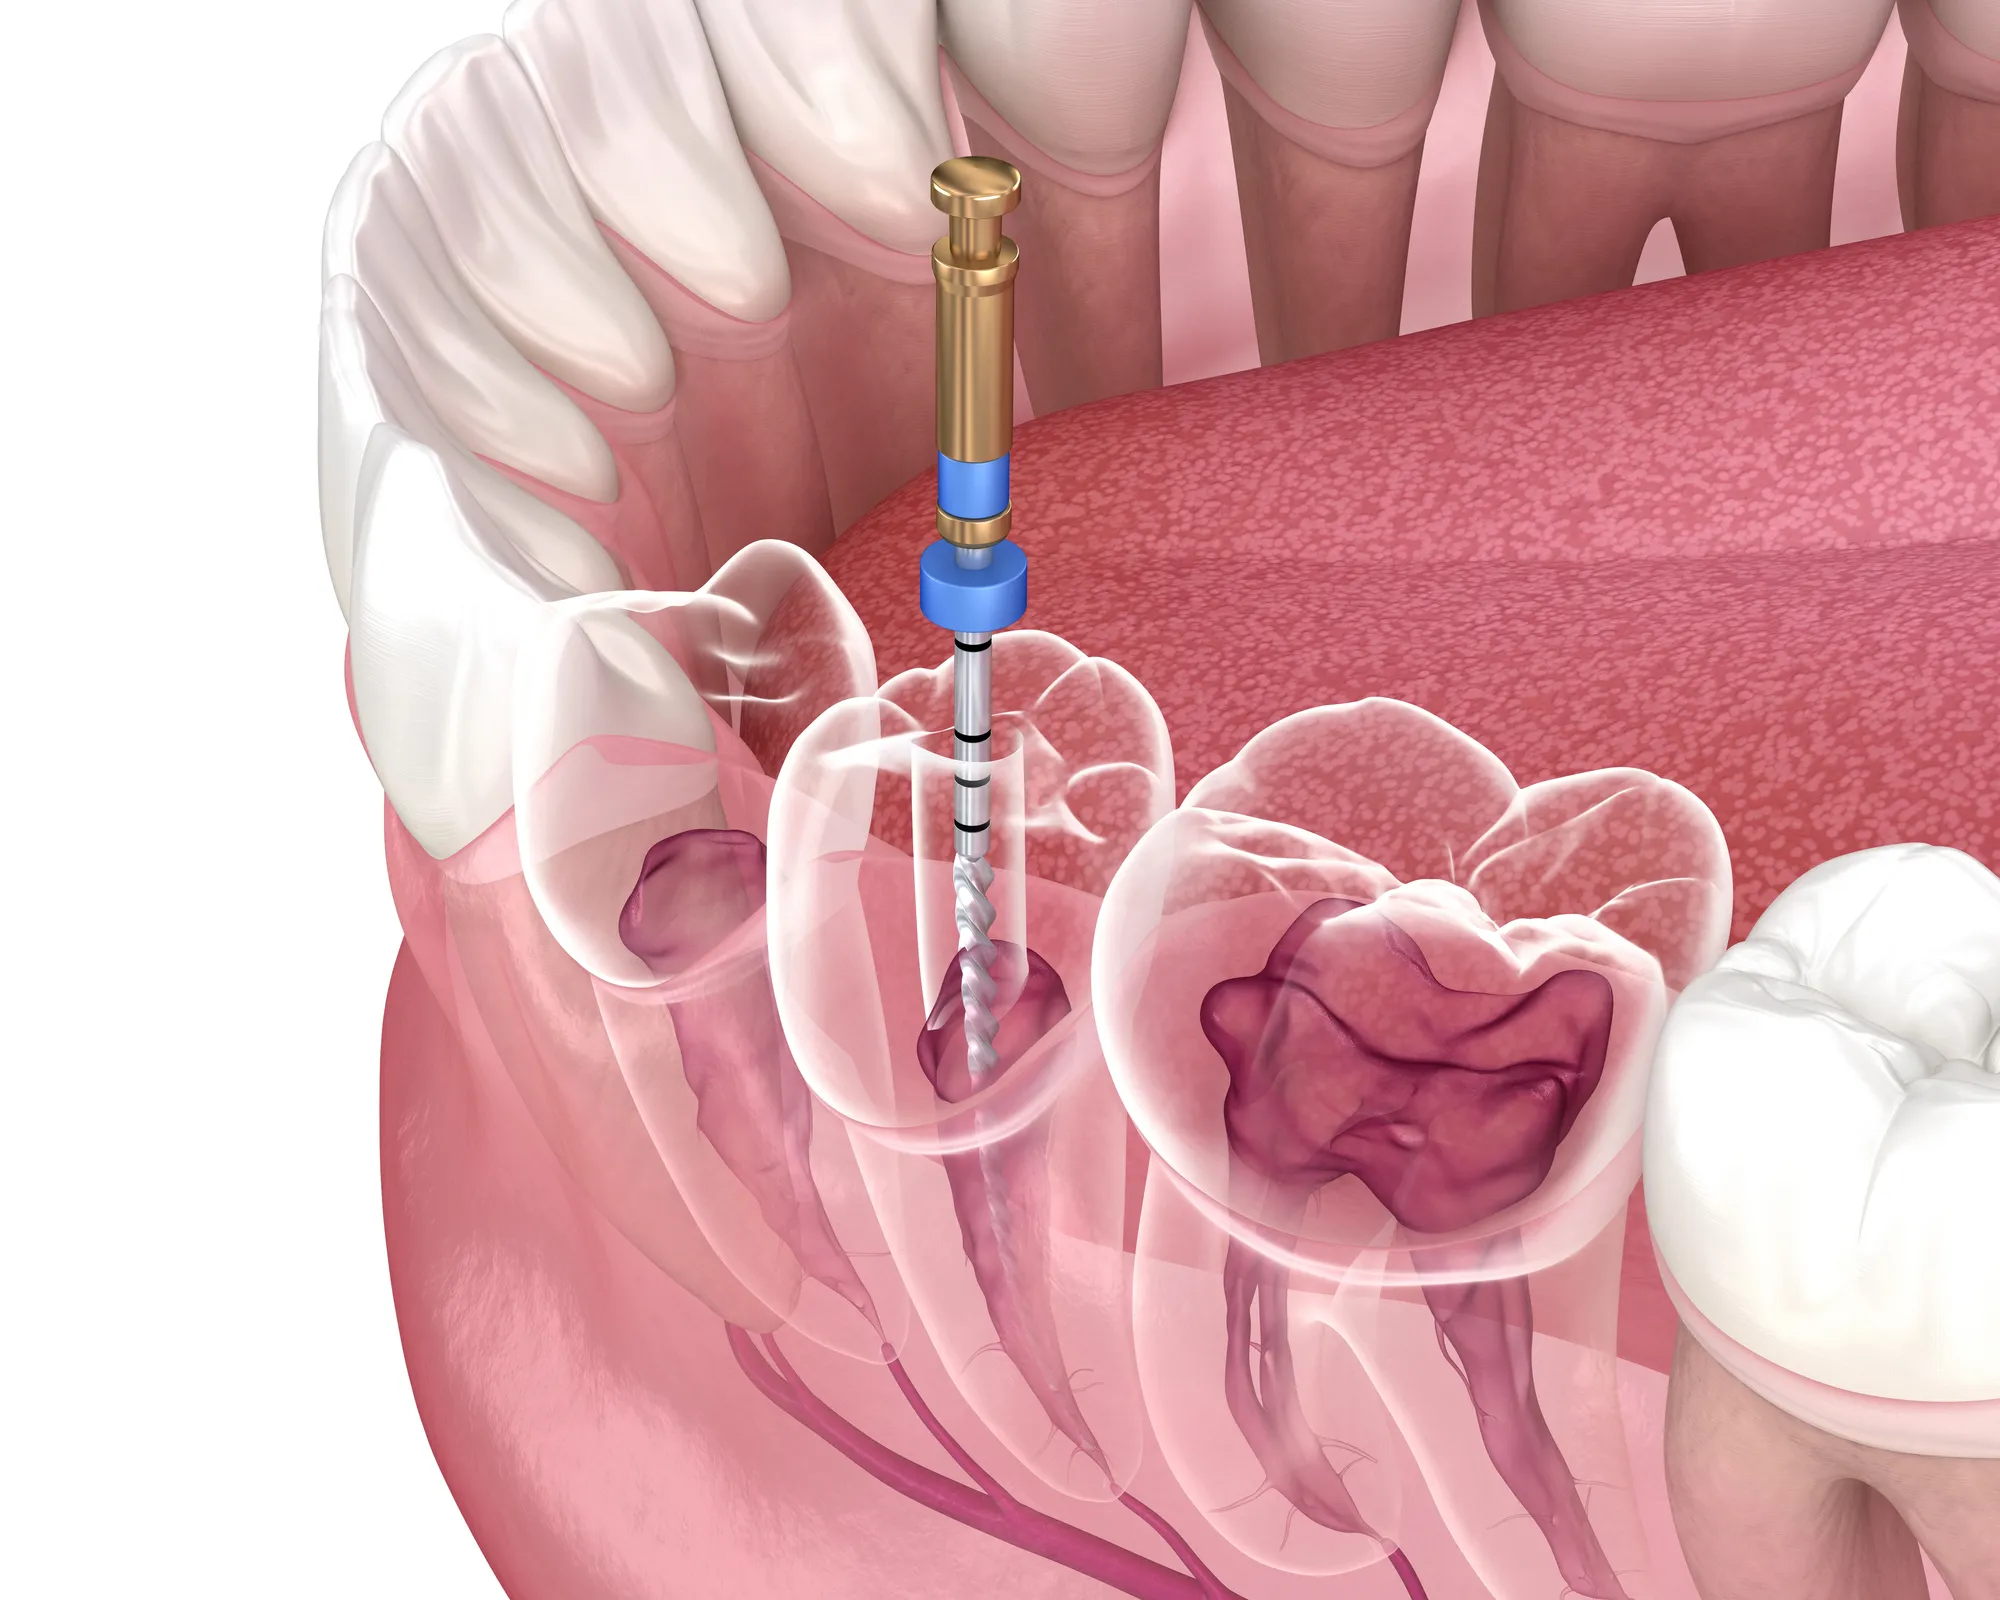

A root canal is a treatment used to repair and preserve a tooth that has been severely damaged by decay or infection.

Inside each tooth is a soft tissue called the pulp, which contains nerves and blood vessels. When this tissue becomes inflamed or infected, it can cause significant discomfort and, if left untreated, more serious complications.

During the procedure, we numb the area, remove the affected pulp, clean and disinfect the inside of the tooth, and then seal it to prevent more damage. We often place a crown afterward to strengthen the tooth and restore normal function.